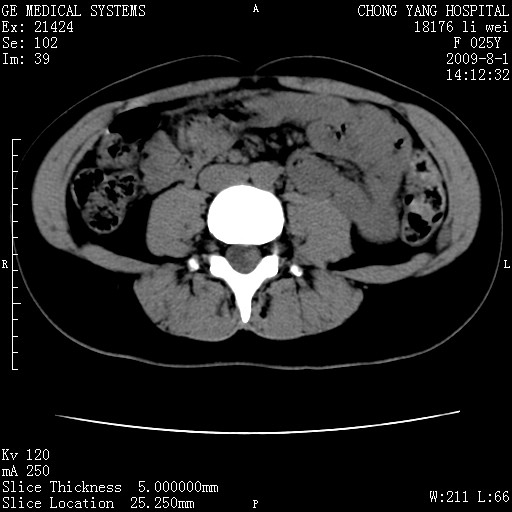

以下是引用pujunzhi在2009-8-1 20:23:00的发言:[br]胸椎旁及背部肌间良性病变,范围广,边界清,沿肌间生长,考虑淋巴管瘤、血管瘤,建议增强扫描。

以下是引用拾荒者在2009-12-30 21:45:00的发言:[br]ct21383:神经纤维瘤病( nf) [br] [br] 神经纤维瘤病。四肢都有,影响美观,四肢上的手术了。[br] [br] [br]谢谢!